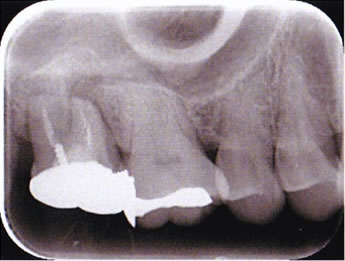

治療後のレントゲン 2方向から撮影してます。

術前のレントゲンと比較し、緊密に薬が詰まっています。